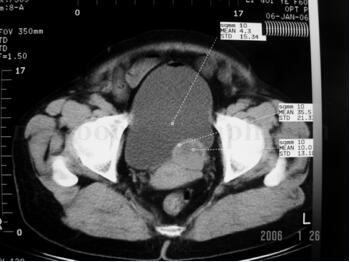

CT:CT检查示膀胱左侧壁占位病变(图33-1)。

图33-1 CT示膀胱左侧壁占位病变